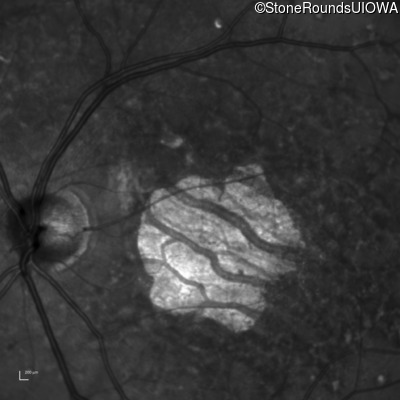

Infrared Fundus Photograph - Right - 20/125

Exemplar